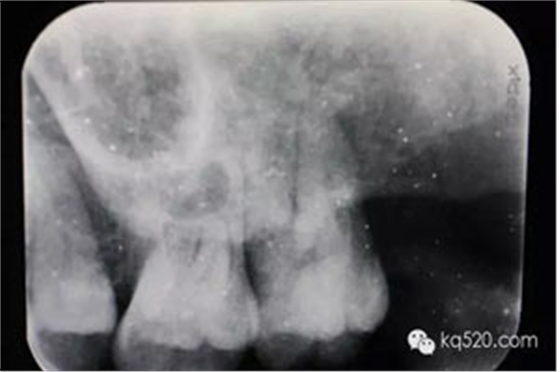

圖2.根尖片檢查:28遠(yuǎn)中水平阻生,看不清28牙根與上頜竇的關(guān)系,建議拍全景片。